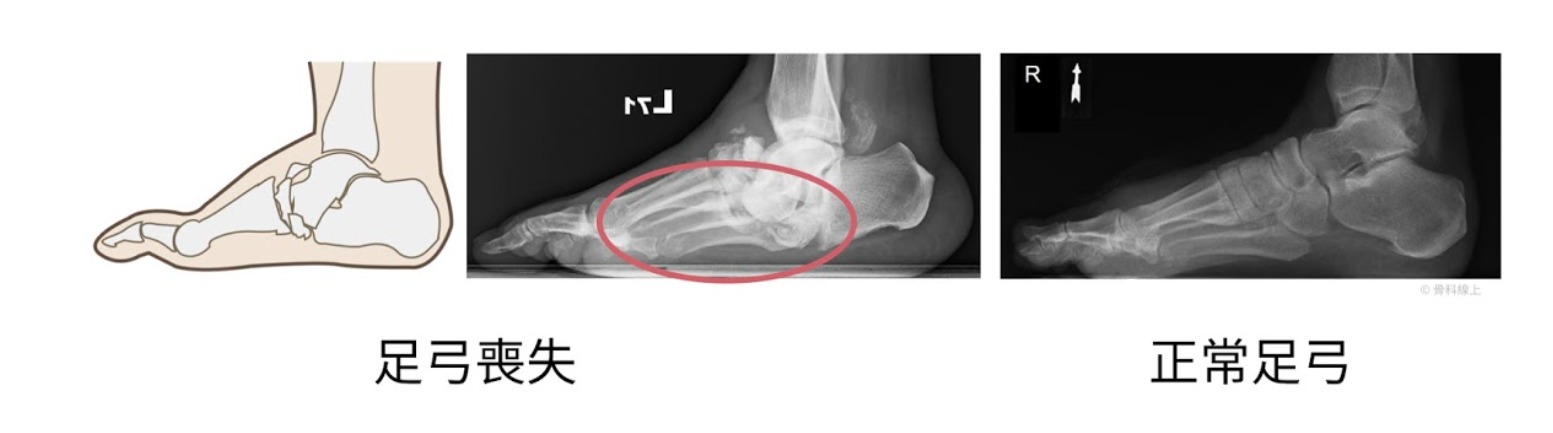

68.一位長年有糖尿病史的患者,近日因足踝腫脹疼痛前來就診,醫學影像顯示有夏柯氏關節病變(Charcot arthropathy) ,發現在足底處已有壓瘡,使用下列何種處置最不合適?

(D)UCBL (University of California Biomechanics Laboratory) 硬式裝具